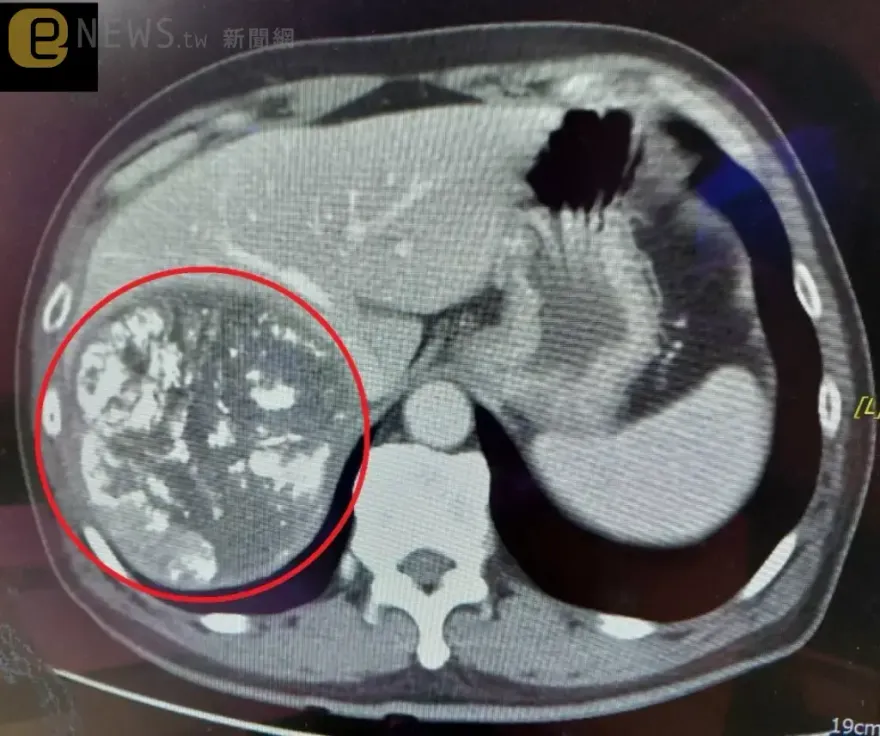

肝癌

上腹痛

腫瘤

B型肝炎

巨大惡性腫瘤

壓迫下腔靜脈